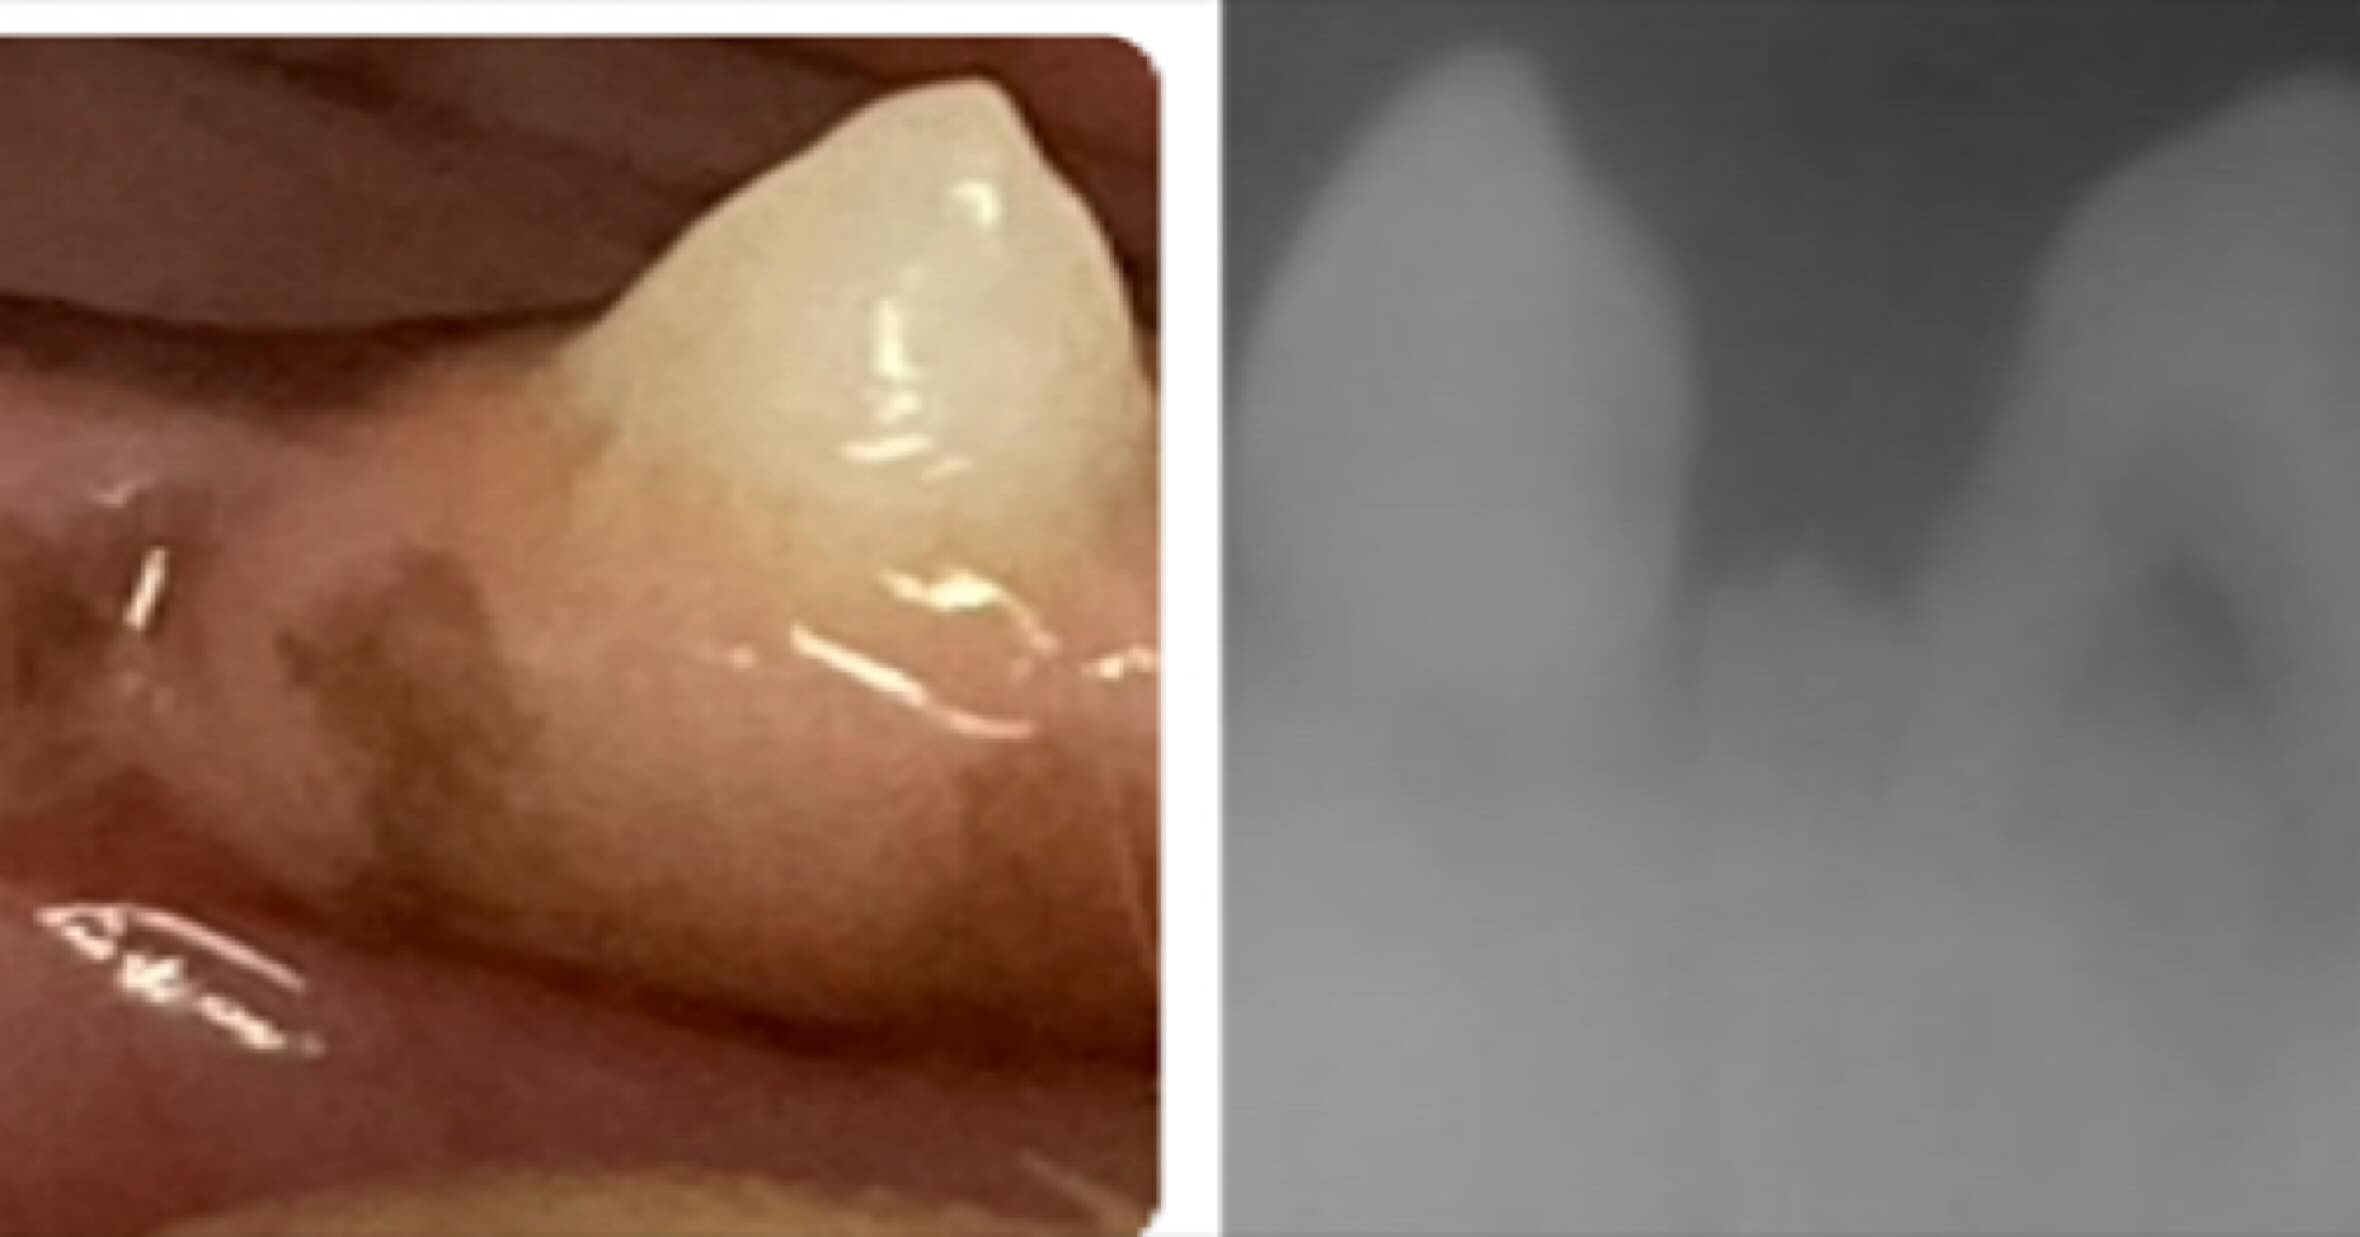

歯周疾患診療

人と同じように犬猫も口腔内環境が重要です。

【それ本当?】 第7回 猫は歯周病になりにくいって本当? ⸻ 「猫は歯周病になりにくいって聞いたから安心」 そう思っていませんか?🐱 実は猫でも 👉 歯周病はと...

【それ本当?】 第7回 猫は歯周病になりにくいって本当? ⸻ 「猫は歯周病になり...

【それ本当?】 第6回 歯周病は年を取ってからなるって本当? ⸻ 「歯周病って歳を取ってからなる病気でしょ?」 そう思っていませんか?🤔 実はこれ、半分正解で半...

【それ本当?】 第6回 歯周病は年を取ってからなるって本当? ⸻ 「歯周病って歳...